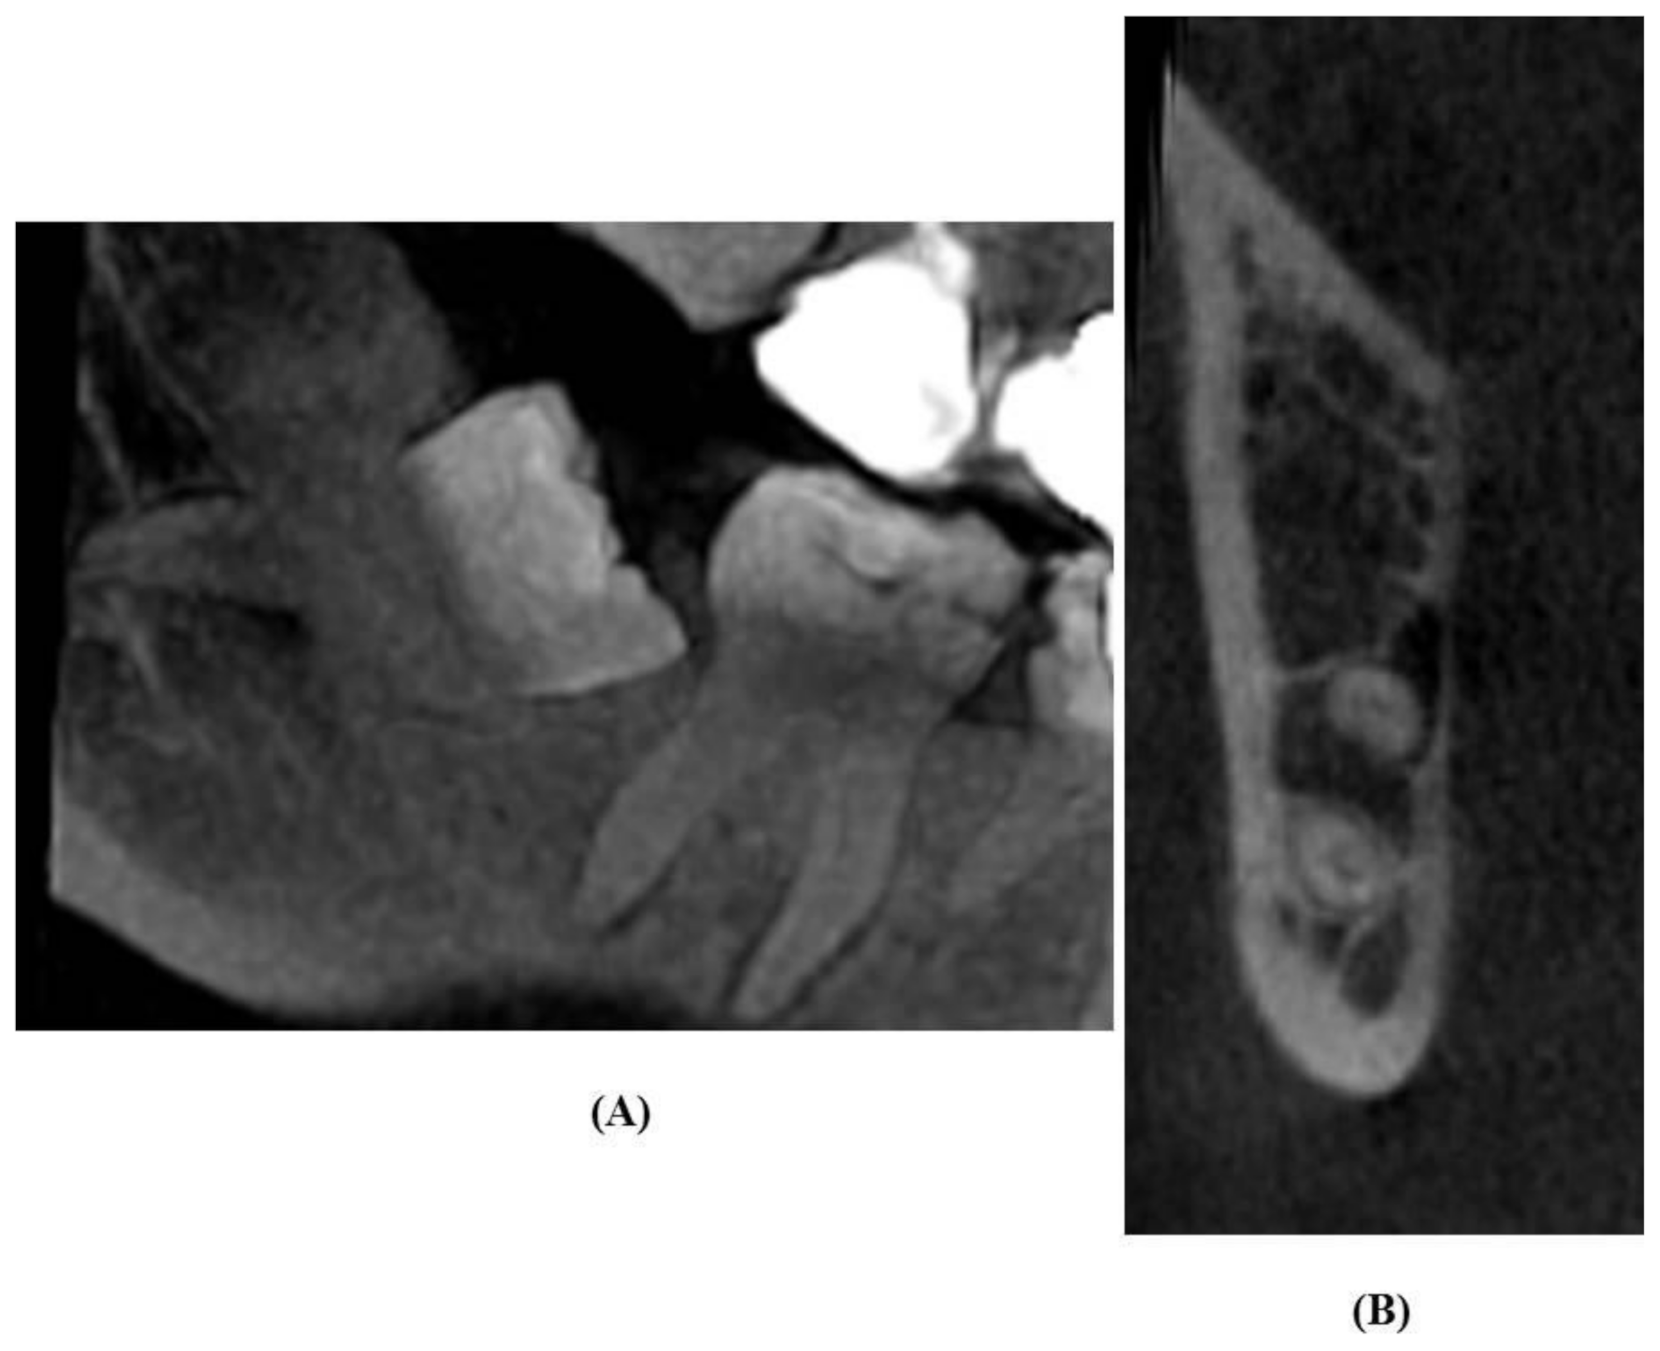

2.4. Evaluation of OPG Images

2.5. Analysis of CBCT Images